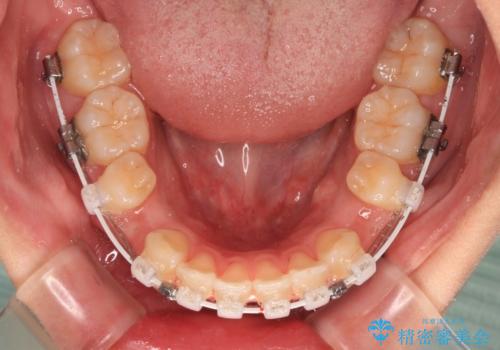

- 矯正装置

- 審美装置

- 全体的なデコボコと口元の突出感を改善したいとのことで来院された患者様です。

このままデコボコを整えるとさらに突出感が増すため、上下左右の第一小臼歯を抜歯し、ワイヤー装置にて矯正しました。